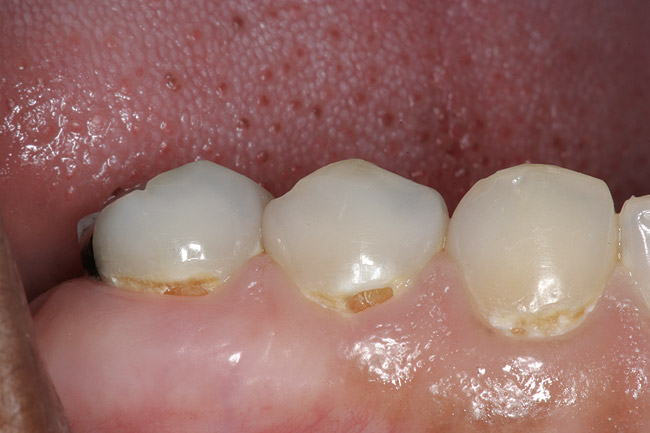

Replacement of existing restorations is responsible for 75% of all operative dentistry.15,19 The reasons for placement and replacement of restorations of direct restorative materials include: primary caries (Figure 1 and Figure 2); recurrent caries (Figure 3); poor margins (Figure 4 and Figure 5); restoration fracture (Figure 6 and Figure 7); tooth fracture (Figure 8); esthetics (Figure 9); non-carious tooth structure lost (attrition, abrasion, abfraction, erosion) (Figure 10); and pain/sensitivity.

Figure 5  Defective margins. Mandibular second molar with a Class II composite resin with a defective facial–gingival margin.

Figure 5

Figure 6  Restoration fracture. Fractured isthmus of an amalgam restoration.

Figure 6

Figure 7  Restoration fracture. Fractured distal marginal ridge of a Class II composite resin restoration on a mandibular second premolar.

Figure 7